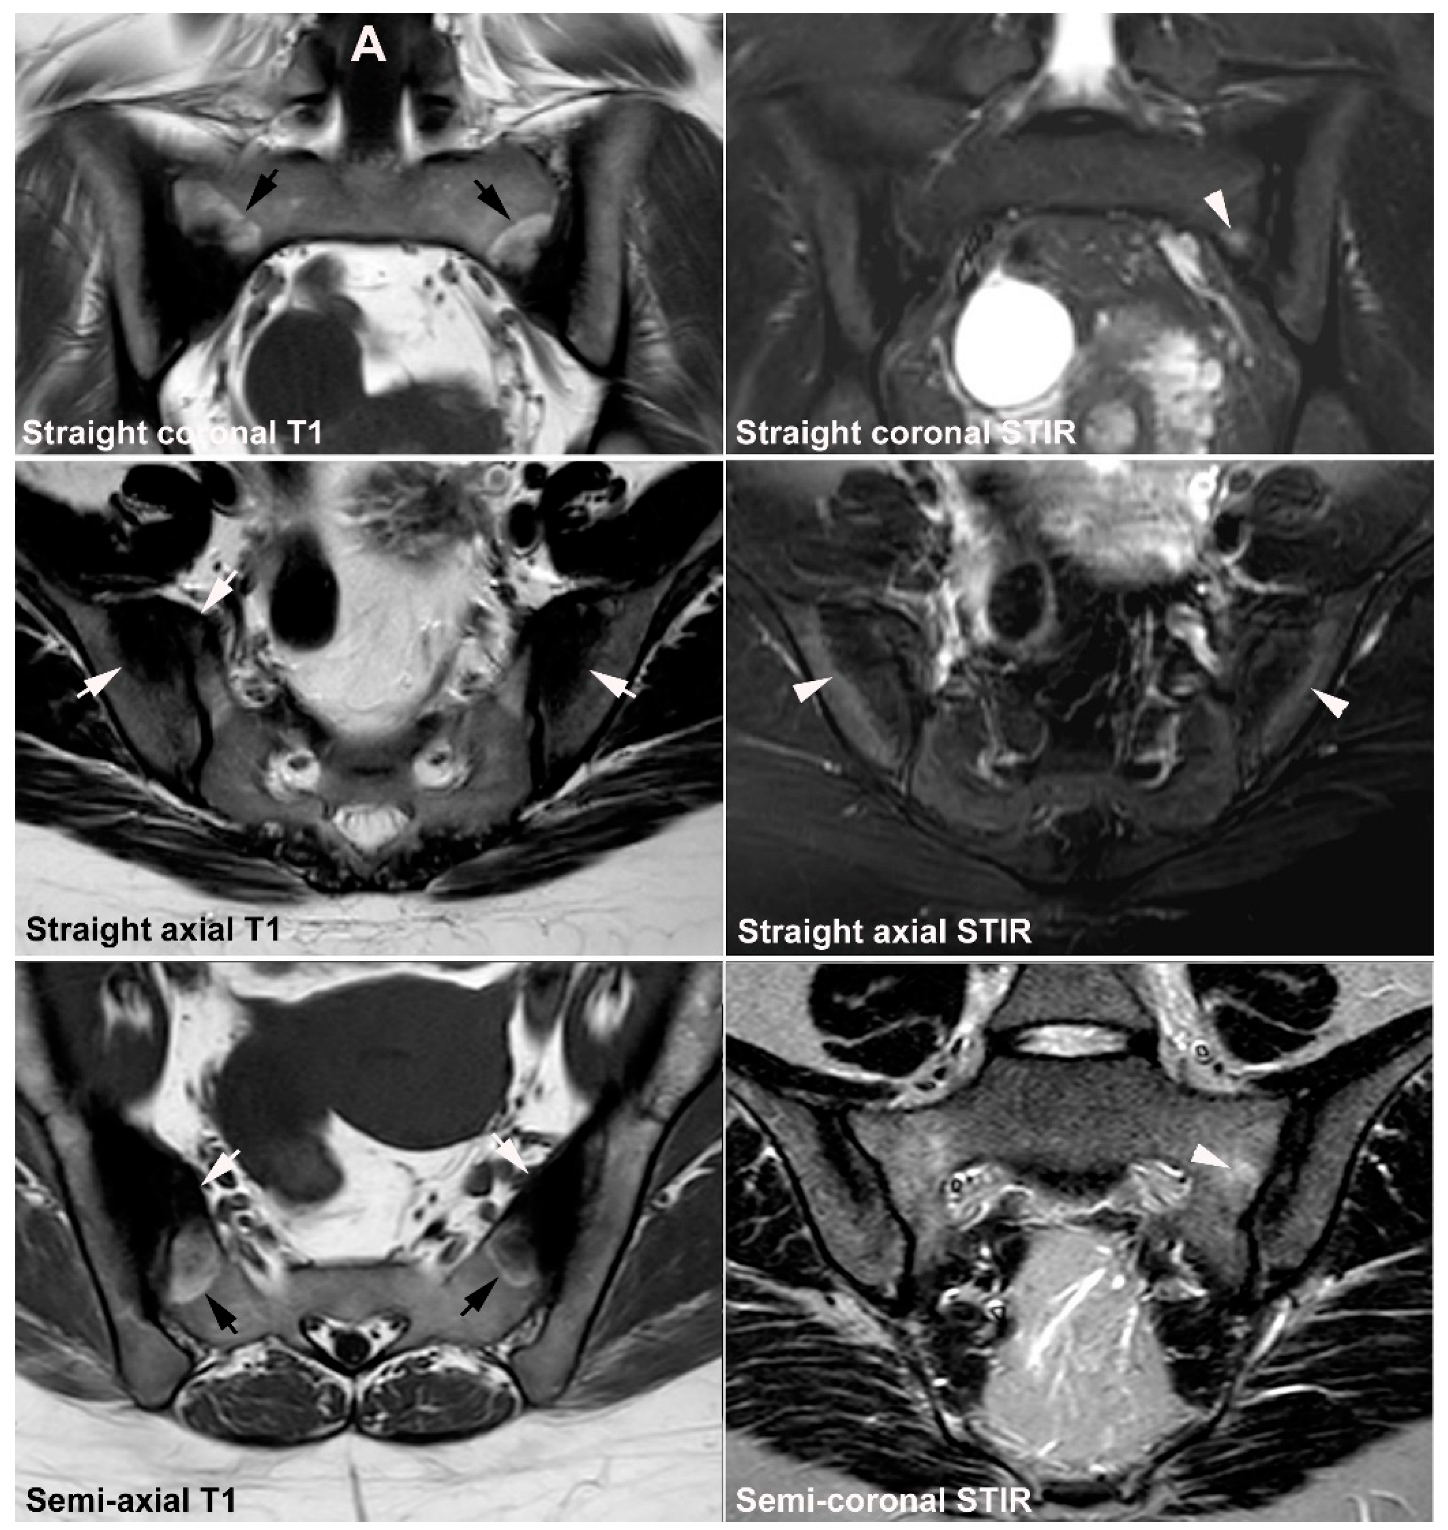

9. Infectious Sacroiliitis

10. Fractures

10.1. Sacral Stress Fracture

10.2. Sacral Insufficiency Fracture